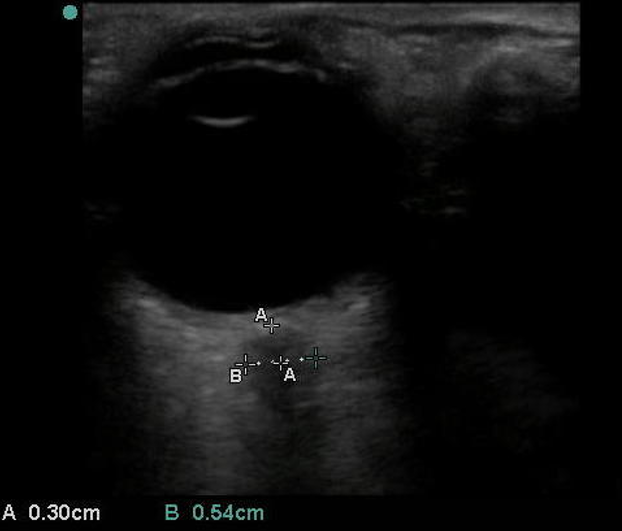

Ocular Dilated Optic Nerve Sheath Diameter Image